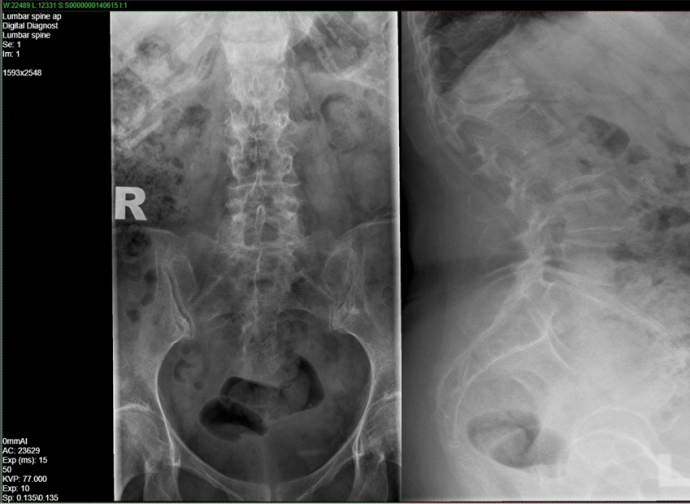

Lumbosacral X-ray after 12 months

No adjacent new fractures observed after 12 months with romosozumab therapy